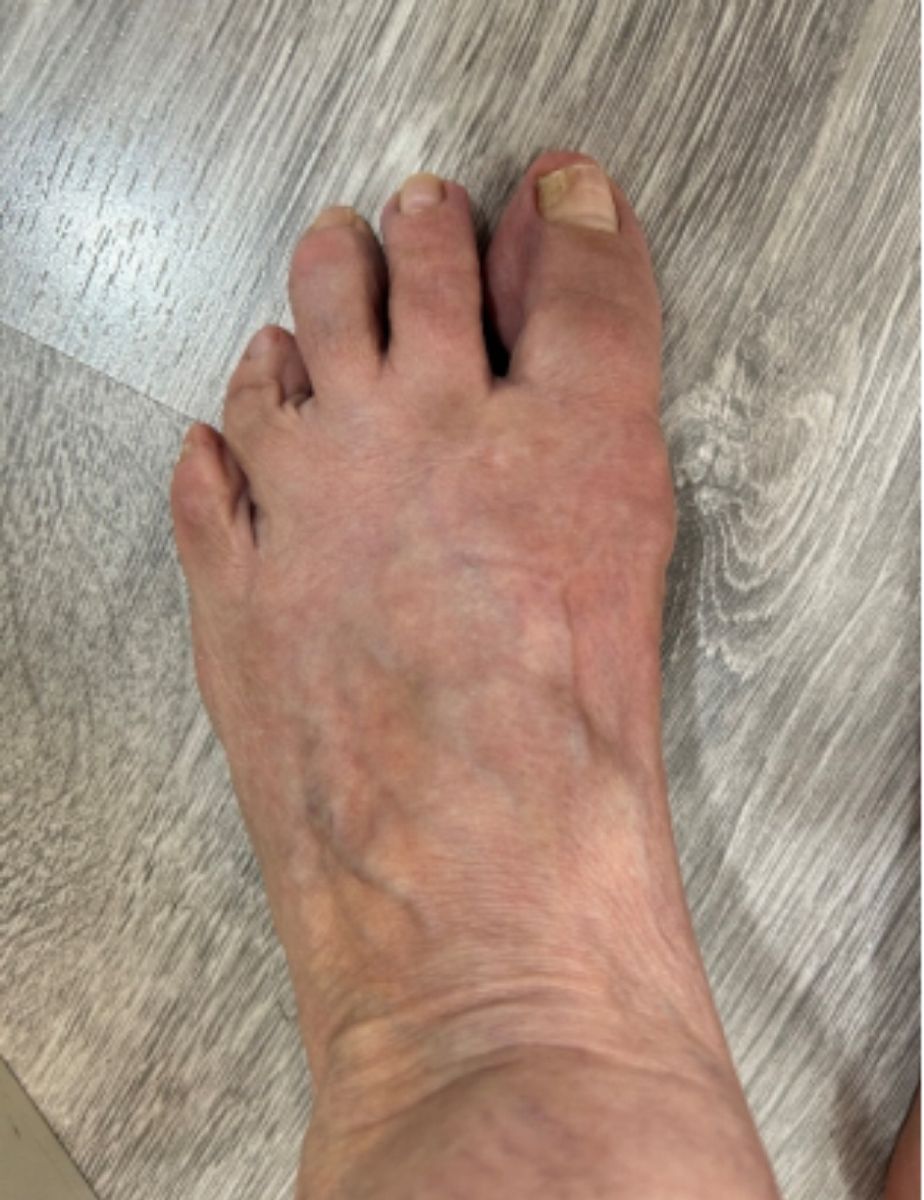

ANTES

casos reales juanetes alicante